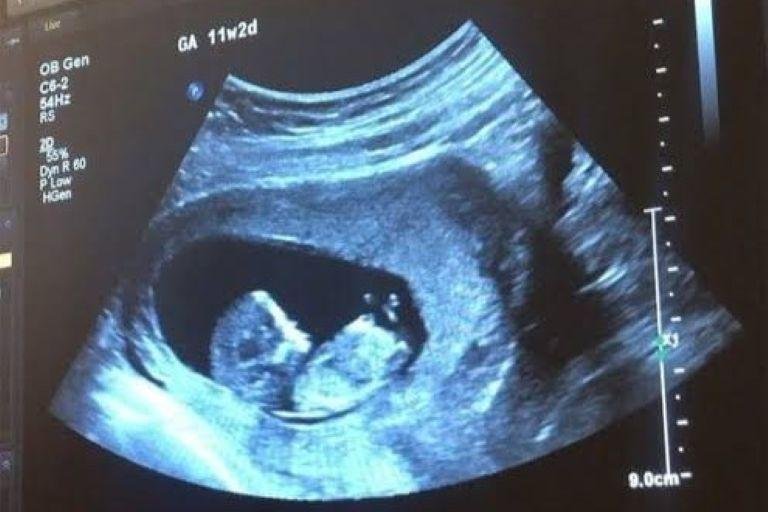

Exames de Ultrassonografia

• Ultrassom Obstétrico

Acompanhamento completo da gestação com exames de alto e baixo risco, incluindo ultrassom obstétrico simples, com Doppler, Doppler com perfil biofísico fetal (PBF) e ultrassom morfológico do 1º, 2º e 3º trimestre.